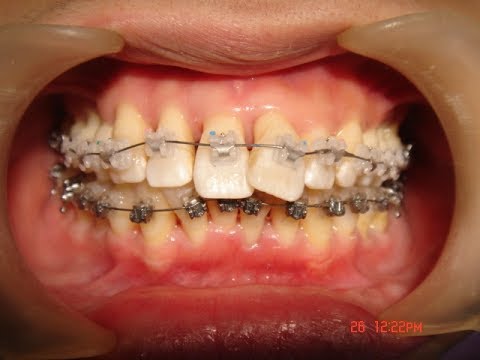

成人矯正の中の、もっと大人の矯正ということで、

歯周病治療のための矯正があります。

歯並びの問題で、清掃性が非常にわるく、

歯周病を悪化させている場合、

さらなる歯周病の進行を予防するため、

50代、60代でも矯正治療をするのです。